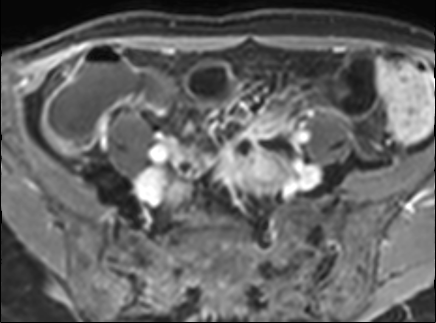

Bệnh nhân nữ 48 tuổi, đang điều trị bằng thuốc kháng TNF, được chỉ định nội soi đại tràng.

Phát hiện hẹp lòng ruột ở đại tràng sigma, không thể vượt qua được khi nội soi.

MR-enterography được thực hiện để đánh giá mức độ lan rộng của chỗ hẹp.

Ruột non bình thường, nhưng ghi nhận các đoạn hẹp ở đại tràng xuống và đại tràng ngang.

Cả hai đoạn hẹp đều có thành ruột dày đến 8 mm và ngấm thuốc rõ rệt theo kiểu niêm mạc ở đại tràng xuống và kiểu phân lớp ở đại tràng ngang.

Giãn ruột trước chỗ hẹp được ghi nhận ở cả hai đoạn.

Do các chỗ hẹp này không hiện diện khi nội soi đại tràng trước khi điều trị kháng TNF, nhiều khả năng chúng đã hình thành trong quá trình điều trị.

Do đó, quyết định phẫu thuật cắt đại tràng gần toàn bộ với miệng nối hồi-sigma đã được đưa ra.